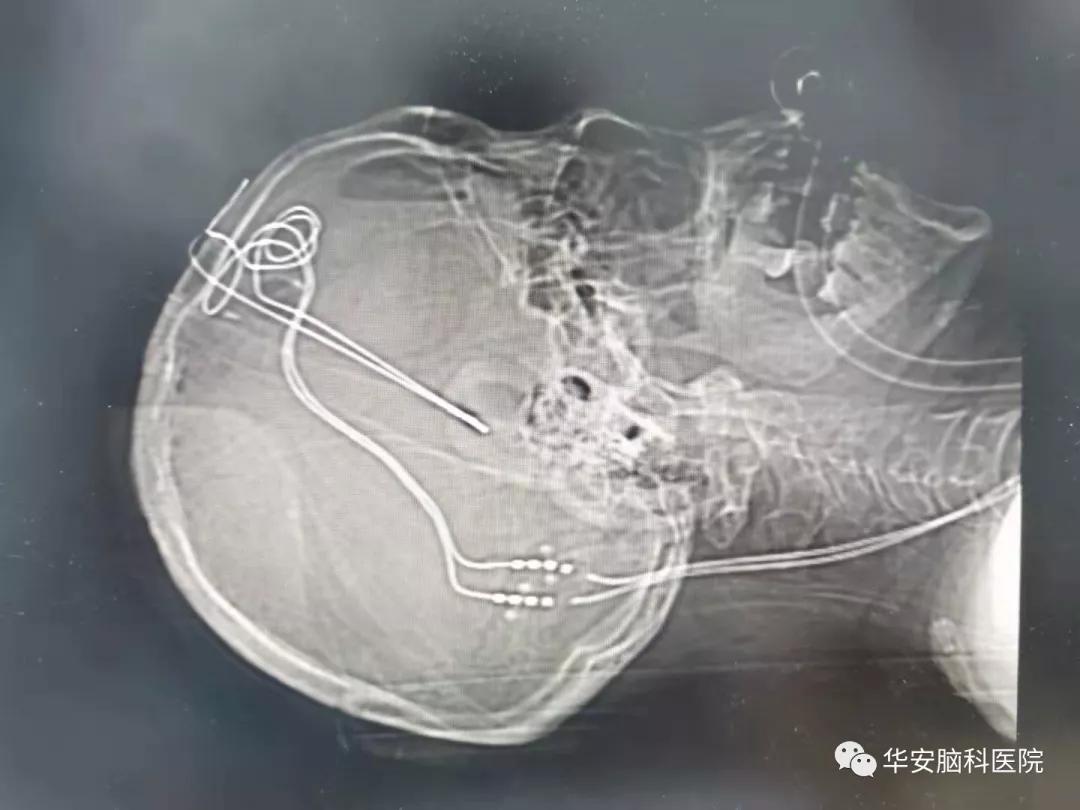

DBS术后影像

傅院长结合患者病史、查体及影像学检查,明确诊断为梅杰综合征,经过专家团队讨论,决定为患者行脑起搏器手术(DBS)。 在傅先明院长的指导下,磁共振引导下的立体定向脑起搏器电极植入手术顺利完成。